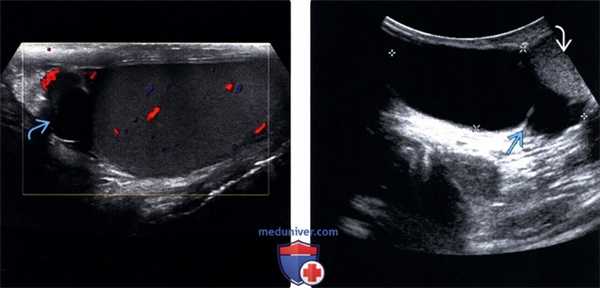

(Слева) Типичные признаки случайно обнаруженной и клинически незначимой кисты придатка яичка. Анэхогенный бессосудистый очаг с нечетким контуром в головке придатка яичка.

(Справа) В правой половине мошонки визуализируется крупная киста придатка яичка (отмечена калиперами) с единичной тонкой перегородкой, смещающая яичко книзу. Обратите внимание, что для выявления этого крупного очага потребовался не высокочастотный линейный датчик, а не абдоминальный датчик.